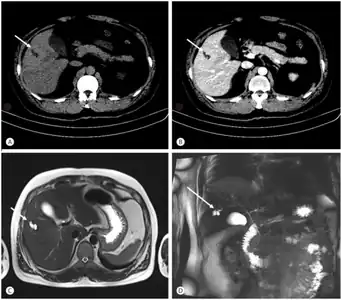

Modern imaging techniques allow the diagnosis to be made more easily and without invasive imaging of the biliary tree.[9] Commonly, the disease is limited to the left lobe of the liver. Images taken by CT scan, X-ray, or MRI show enlarged intrahepatic (in the liver) bile ducts due to ectasia. Using an ultrasound, tubular dilation of the bile ducts can be seen. On a CT scan, Caroli disease can be observed by noting the many fluid-filled, tubular structures extending to the liver.[4] A high-contrast CT must be used to distinguish the difference between stones and widened ducts. Bowel gas and digestive habits make it difficult to obtain a clear sonogram, so a CT scan is a good substitution. When the intrahepatic bile duct wall has protrusions, it is clearly seen as central dots or a linear streak.[10] Caroli disease is commonly diagnosed after this “central dot sign” is detected on a CT scan or ultrasound.[10] However, cholangiography is the best, and final, approach to show the enlarged bile ducts as a result of Caroli disease.

Bileduct dilatation in segment 5 arrow a,b) CT, c) MRI, d) MRCP

Magnetic resonance cholangiopancreatography (MRCP) of Caroli disease, showing cystic dilatations of bile ducts.[1]